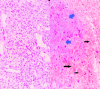

Figure 3

Figure 3. Microscopic images showing clusters of soft epithelioid to spindle cells (black arrow) arranged in nests and cords against a myxoid background (white arrow) (A) and scattered appreciable calcific flakes (blue arrow) (B).

Figure 4

Figure 4. Microscopic images of the tumor showing focal areas of clear cell change seen in some sections (A) and areas of necrosis (blue arrows) and hemorrhages (black arrows) (B).